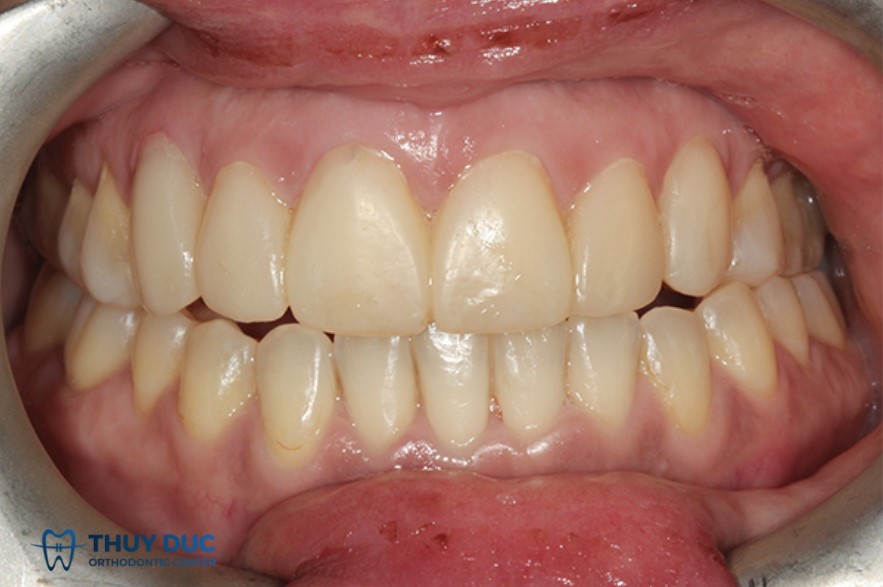

c. Độ chồng răng dọc (Overbite) và độ nhô răng ngang (Overjet) ở mức sinh lý

- Overbite: Là khoảng răng cửa hàm trên phủ lên răng cửa hàm dưới. Mức lý tưởng là khoảng 1 – 2 mm hoặc khoảng 1/3 chiều cao răng cửa dưới.

- Overjet: Là khoảng cách răng cửa hàm trên nhô ra trước so với hàm dưới, lý tưởng cũng khoảng 1 – 2 mm.

Nếu overbite quá lớn → cắn sâu (răng trên che gần hết răng dưới).

Nếu overjet quá lớn → hô răng, có thể ảnh hưởng đến phát âm và thẩm mỹ.

- Class I (chuẩn): Răng cối trên nằm đúng vị trí so với răng cối dưới.

Class I là dạng khớp cắn được xem là chuẩn và lý tưởng nhất.